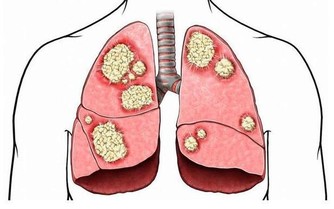

此外,Hp也被世界衛生組織列為胃癌的I類致癌物。

研究發現,Hp感染跟胃癌的發生有較為密切的關係,一旦感染Hp,再合併胃部的一些慢性炎症,將來發生腫瘤的概率比正常人高。但如果根除幽門螺桿菌,便可降低約39%的胃癌發生風險。